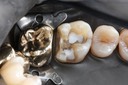

Gary Umeda #3 amalgam removal